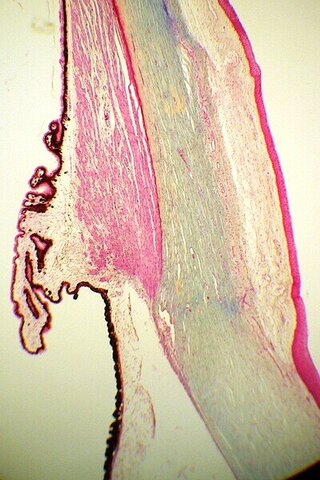

Dies ist ein Längsschnitt durch das kugelige menschliche Auge. Der Schnitt geht genau durch den Blinden Fleck, nicht jedoch durch den Gelben Fleck. Auch die Linse ist nicht im Bild. Hornhaut, Ziliarmuskel, Retina, Aderhaut und Lederhaut sind perfekt getroffen.

Auch die Hornhaut (Cornea) ist sehr gut durchlässig für Licht. Gemeinsam mit dem Kammerwasser leistet sie einen wesentlichen Beitrag für die Lichtbrechung. Durch die Veränderung der Form der vorderen Hornhaut kann man Fehlsichtigkeiten korrigieren (Hornhautlasern). Das vordere Epithel ist mehrschichtig, das hintere Epithel ist einschichtig. Das Präparat ist 400fach vergrößert und gefärbt. Die Spalten zwischen den vielen Zellen sind durch die Präparation entstanden, eine lebende Hornhaut ist lückenlos.